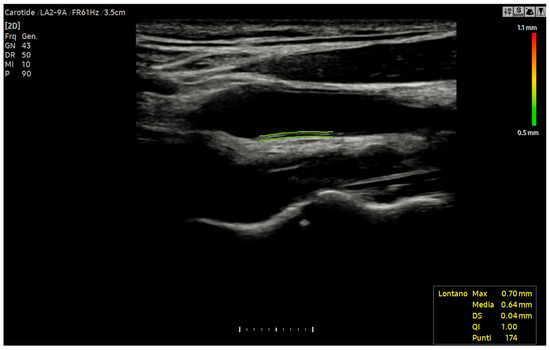

6.4. Carotid Intima-Media Thickness